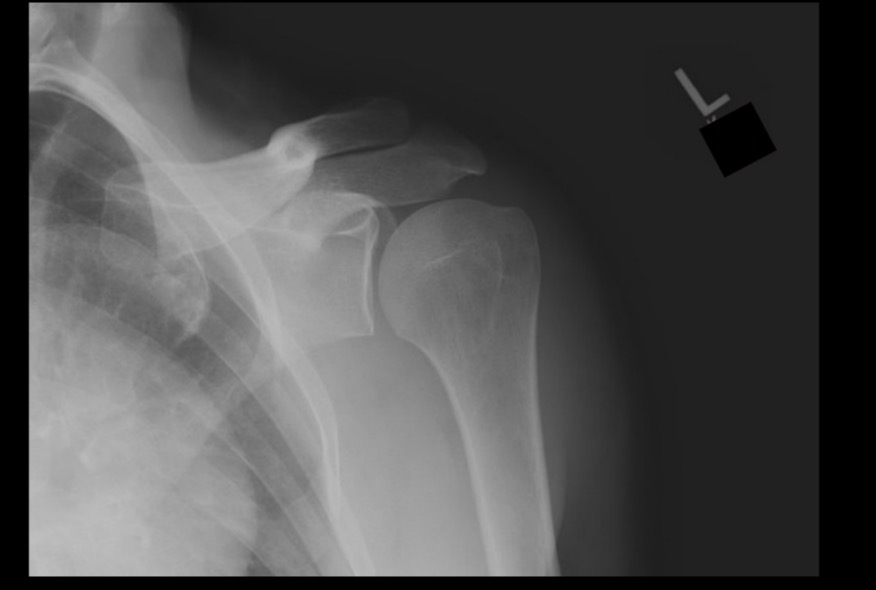

What projection position is this image?

AP LPO Grashey, left